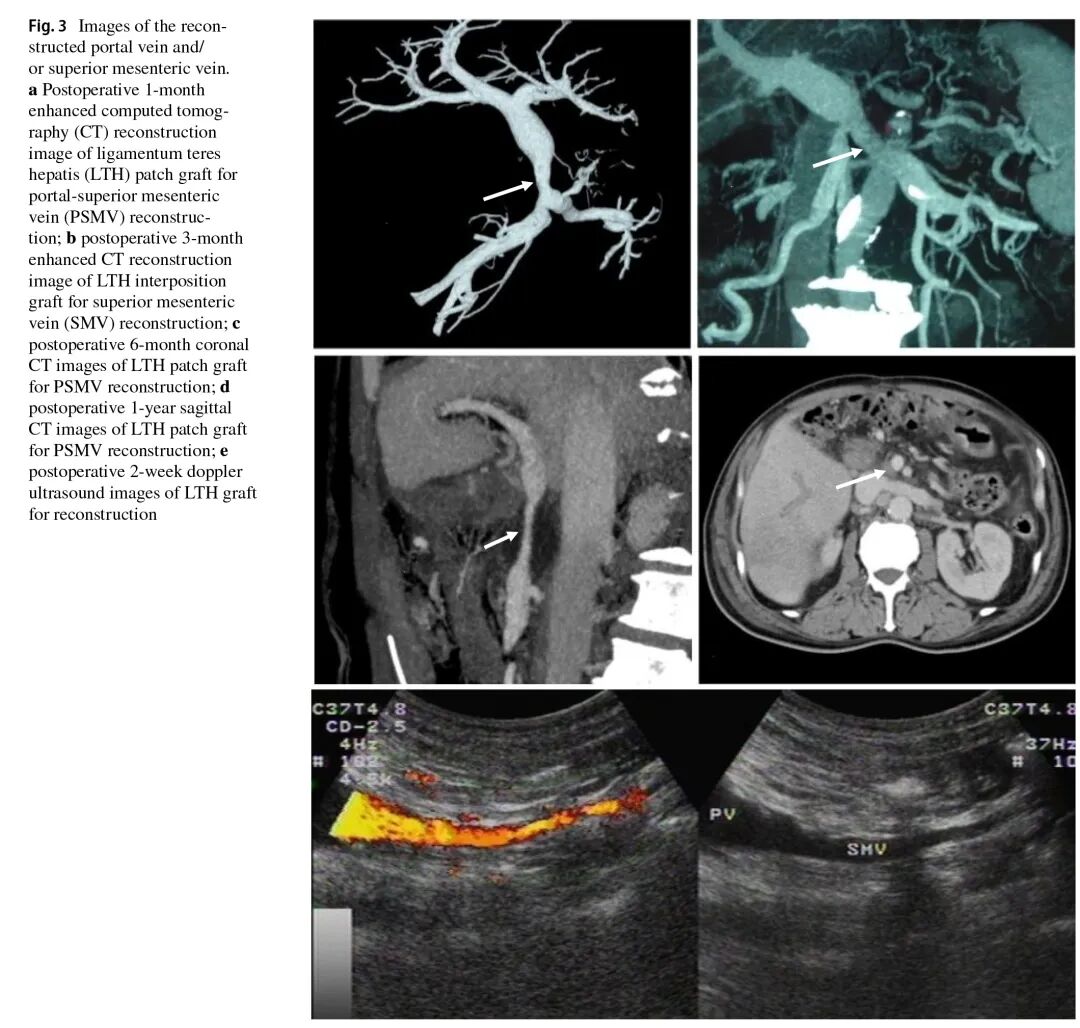

近日,滨州医学院附属医院陈强谱主持开展的成人自体肝圆韧带重建门静脉、肠系膜上静脉的研究正式发表于外科肿瘤学权威期刊《Annals of Surgical Oncology》(肿瘤外科年鉴),标志着医院在该技术领域已达到国际领先水平。论文题目为“Evaluation of Clinical Outcomes and Graft Patency Following Venous Resection and Vascular Reconstruction Using a Recanalized Ligamentum Teres Hepatis Graft in Pancreaticoduodenectomy”。滨医附院胆胰外科病区副主任朱文涛博士及在校研究生刘志伟为共同第一作者,肝胆胰外科多位医师共同参与,陈强谱教授为通讯作者。《Annals of Surgical Oncology》是美国肿瘤外科学会的官方会刊,国际肿瘤外科领域的顶级期刊。

独辟蹊径:化“废弃组织”为“血管桥梁”。在胰十二指肠切除术中,门静脉及肠系膜上静脉的切除重建一直是外科领域的难点。传统方案多依赖人工血管或异体血管,存在免疫排斥、费用高昂、远期通畅率不佳等局限。陈强谱教授团队另辟蹊径,将目光投向肝圆韧带——这一源自胎儿时期左脐静脉闭锁的“人体废弃组织”。团队创新性地通过人工扩张技术使其再通,将其转化为理想的血管重建材料。该方案具有三重优势:取材便捷,可在腹部手术中同期获取,不增加额外创伤;安全性高,作为自体组织彻底规避免疫排斥风险,其独特的组织学特性为血管愈合提供天然基础;经济可行,显著降低患者经济负担和医保资金压力,实现医疗效益与社会效益的统一。

自2003年起,团队便开始探索并使用扩张再通的肝圆韧带进行门静脉及肠系膜上静脉重建。经长期随访证实,该技术术后血管通畅率理想,临床效果显著。陈强谱教授团队进行的基础研究亦表明,肝圆韧带在管径、组织学结构及生物力学特性上与门静脉及肠系膜上静脉高度相似,其内表面有内皮细胞覆盖,为良好的血管愈合提供了天然基础。作为一种自体组织移植材料,它彻底规避了免疫排斥风险,同时大幅减轻了患者的经济负担和医保资金压力,实现了医疗效益与社会效益的统一。